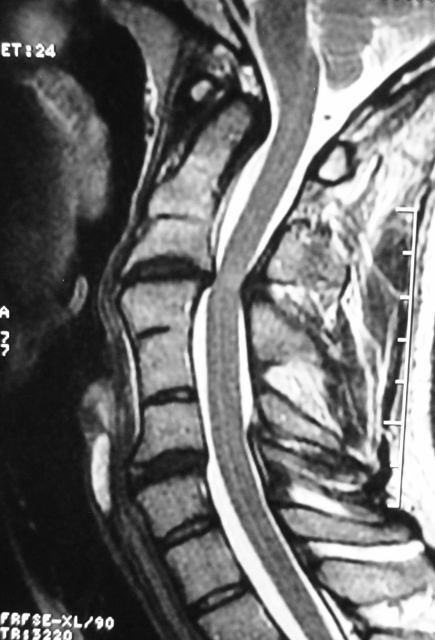

Klippel-Feil Sendromu Servikal MRG

Resim 2: Servikal MRG'de C3-C4 mesafesinde omuriliğe önden ve arkadan bası ve bu seviyede omurilikte sinyal değişikliği görülmektedir.